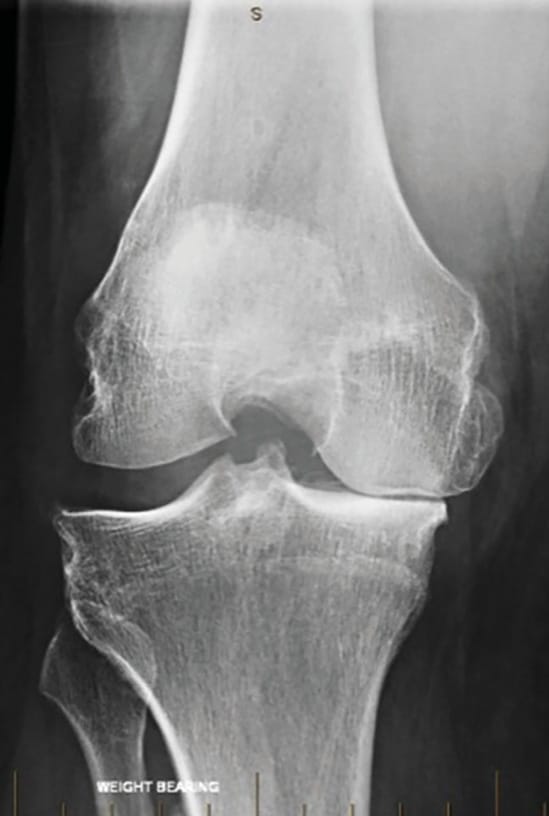

In the clinic we ensure the patient is suitable - typically the younger, more active patient with medial compartment OA, who experiences pain with medial compartment loading, and has radiographic evidence of >50% medial joint space loss (Figure 2). We exclude patients with symptomatic OA of the lateral compartment, those with inflammatory arthritis, and those with a fixed flexion deformity of >10° or flexion range <90°. Age, weight and WOMAC score are important factors that will be discussed further. It is important to pre-operatively demonstrate the pain experienced with varus loading through the medial (diseased) compartment, and the relief of pain on valgus loading through the lateral compartment; this confirms the suitability of the patient for HTO, and is instructive to the patient. Finally, we assess integrity of the MCL, making note of patients with more than 3mm of laxity to valgus stress.